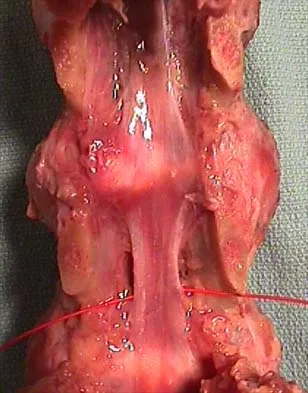

Figures 1a through 1c show the radiograph and MRI scans of a 16-year-old patient who has a painful hip. Examination reveals a significant limp, limited abduction and internal rotation, and severe pain with internal rotation and adduction. A biopsy specimen is shown in Figure 1d. What is the deposited pigment observed in this condition?